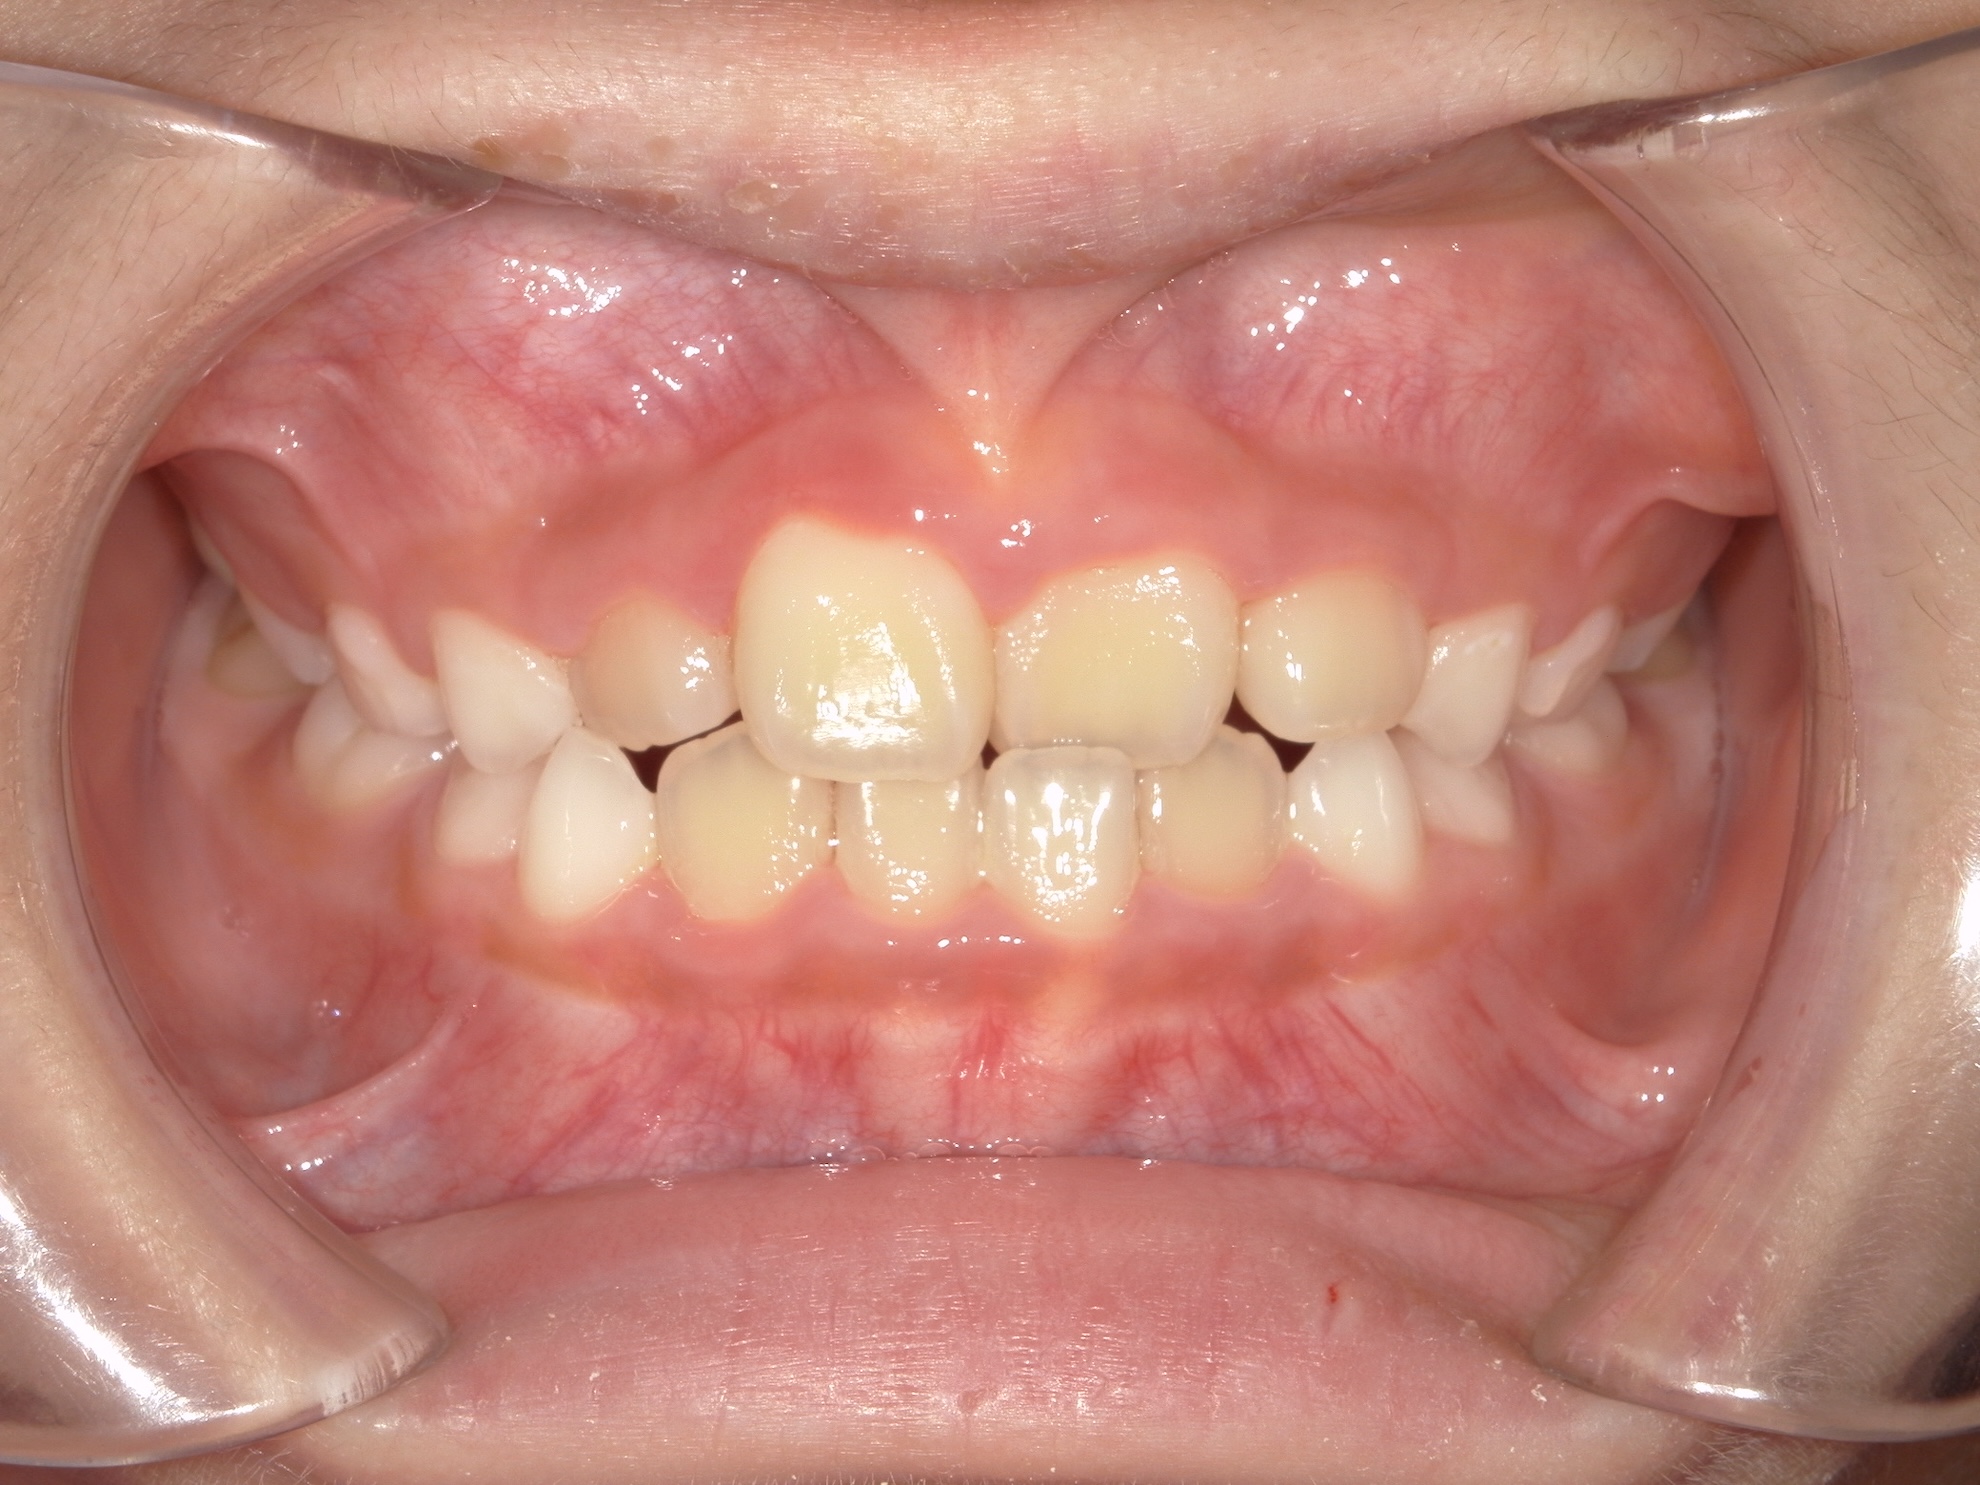

交差している歯並びを改善しました

BEFORE

交差した歯並びの治療前

AFTER

交差した歯並びの治療後

年代・性別

8歳 女の子

主訴

前歯の歯並びが気になる

診断

骨格性Ⅰ級、歯性Ⅰ級、前歯部クロスバイト(一部)、前歯部叢生

治療内容

拡大床(弾線付き)、部分的な唇側ワイヤー矯正、リテーナー

治療期間

2年半

治療リスク

痛み、歯根吸収

治療費用

約40万円